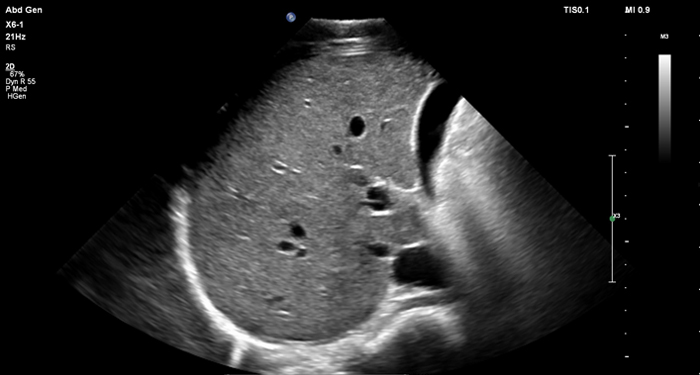

At the touch of a button, the new MaxVue high-definition display brings extraordinary visualisation of anatomy with 1,179,648 additional image pixels compared to a standard 4:3 display format mode. MaxVue enhances ultrasound viewing during interventional procedures and provides 38% more viewing area to optimise the display of dual, side/side, biplane, and scrolling imaging modes.

MaxVue offers a 38% greater viewing area.